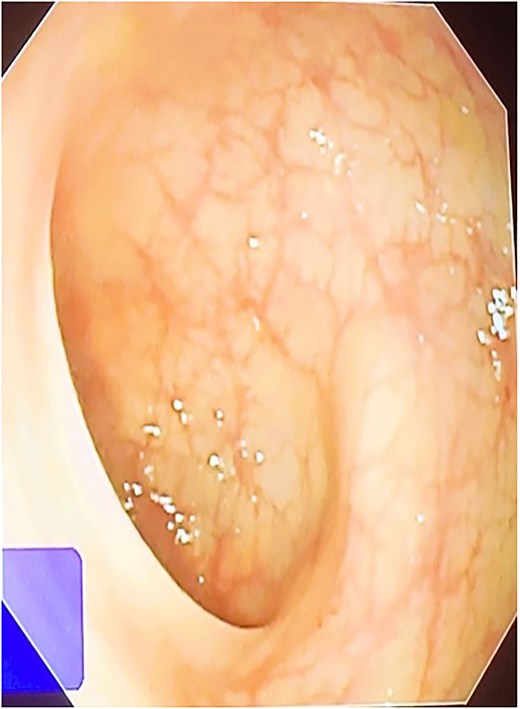

A 42-year-old male patient presented with discharge from anal regions accompanied with pain. Upon rectal examination, an internal opening was observed at 6 o’clock, ~2.5 cm above the anal verge. The external opening was located on the right thigh, 18 cm away, with an indurated tract beneath the skin. Proctoscopy revealed pus discharge from the internal opening. All relevant pre-operative investigations were done (Fig. 1).